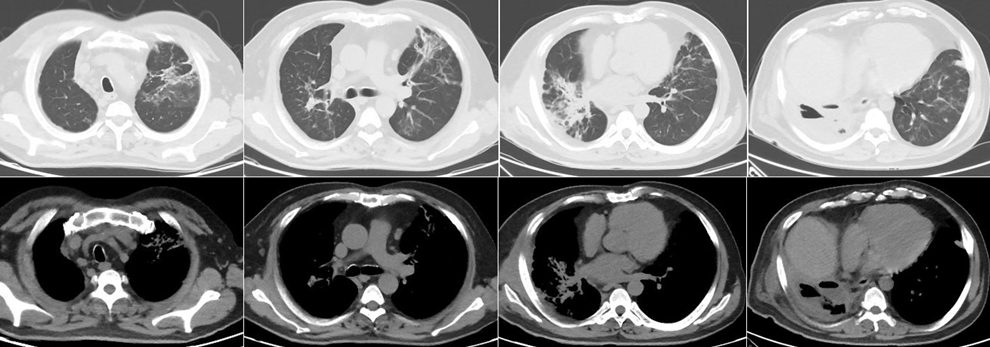

• 4月5日于我院急诊就诊,测体温38.5℃。动脉血气分析(FiO2 0.29):pH 7.473,PaO2 57.2 mmHg,PaCO2 34.6 mmHg。急诊化验:WBC 14.99×109/L,NEU% 91.8%,LYM 0.61×109/L,血钠127 mmol/L,D-二聚体7470 ng/ml,C反应蛋白(CRP)350.7 mg/L,白介素-6(IL-6) 283.1 pg/ml,降钙素原(PCT)<0.5 ng/ml。胸部CT:右肺多发感染、实变,空洞影伴液平形成,伴右侧少量胸腔积液、部分包裹,左肺下舌段炎性灶(图1)。胸腔超声:右侧胸腔可见液性暗区,最深约6.0 cm,内可见大量分隔,部分区域呈蜂窝状。急诊以“重症肺炎(右侧)肺脓肿”收入我科。

图片

图1  患者胸部CT(2020年4月5日)